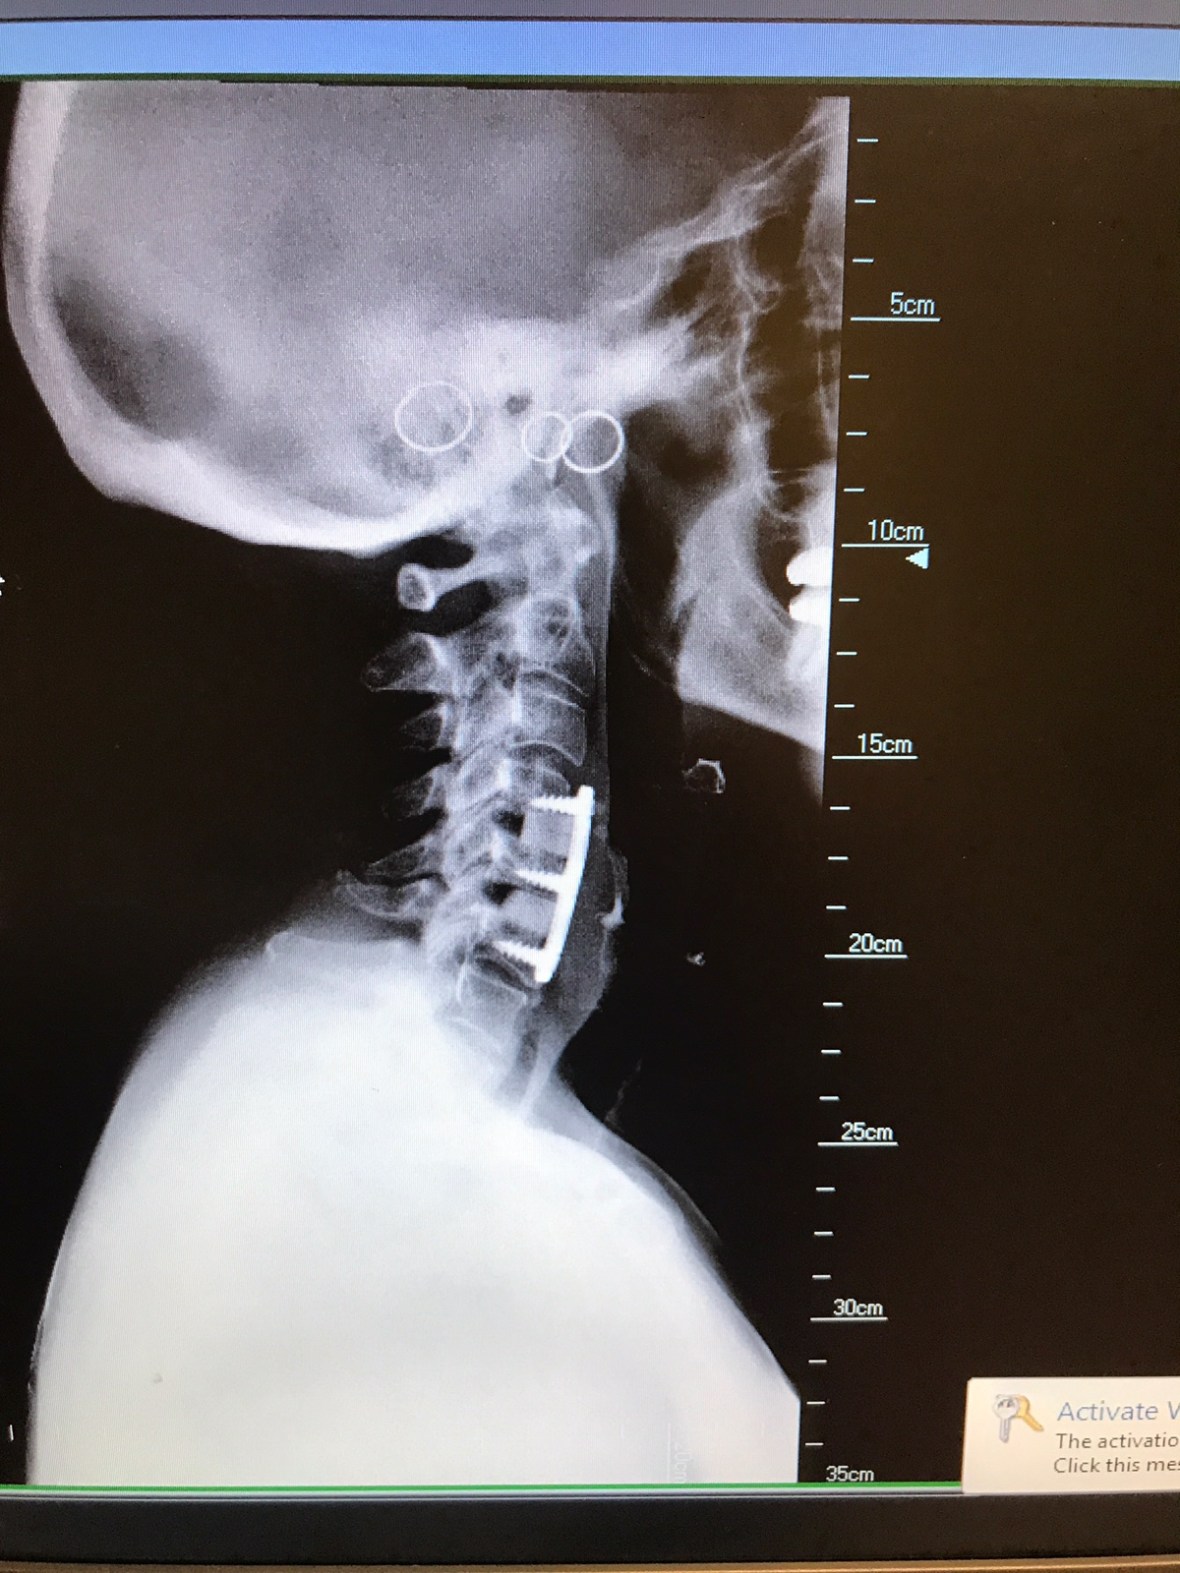

About a year before my diagnosis an MRI showed something suspicious in my C-spine (medical term for neck connected to the spine ) and I was referred to a great surgeon. Patients come from other states to see him. The pictures showed my spine was crushing the nerves in my neck, with “A LOT” of arthritis. Surgery was my choice but it would get worse over time.